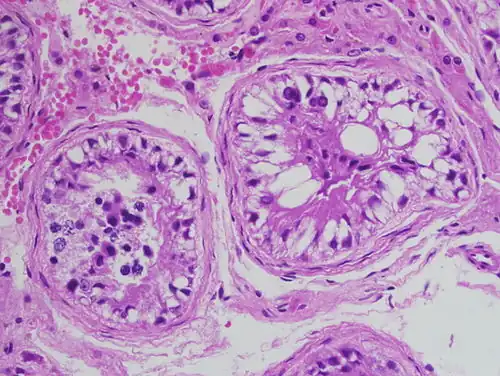

La gametogenesi è il processo a cui sono destinate le cellule germinali per generare cellule sessuali pronte per la riproduzione dell'individuo. Nella femmina si parla di ovogenesi, che da un ovogonio porta a un ovulo e tre globuli polari (almeno nella maggioranza delle cellule che fanno riproduzione sessuata), mentre nel maschio di spermatogenesi, che da uno spermatogonio immaturo forma quattro spermatozoi completi. I due processi sono completamente diversi in tempistiche, modalità ed esiti, per quanto consistano fondamentalmente in divisioni meiotiche inserite nell'ambito di processi differenziativi[24].

Le gonadi sono gli organi che sostengono e proteggono le cellule germinali sia che si impegnino nei processi differenziativi, sia che si dividano per mantenere la popolazione di cellule germinali staminali. Il tutto avviene secondo stimolazione ormonale, sia proveniente dall'organo stesso, sia da ghiandole esterne alla gonade stessa[30]. Nei mammiferi il differenziamento nelle gonadi nelle strutture ovariche o testicolari primitive è segnato proprio dall'invasione delle creste gonadiche primitive delle cellule germinali primordiali (PGC) e dipende, ovviamente dalla coppia di cromosomi sessuali dell'individuo[30]. Un embrione maschio dirige le cellule nella futura midollare del proto-testicolo, un embrione femmina nella regione corticale[30].

Le cellule germinali primordiali proliferano e migrano verso le creste gonadiche che si formano lungo la splancnopleura (quinta settimana)[30], il mesoderma situato attorno all'intestino primitivo, dove vengono inglobate, formando i primi abbozzi delle gonadi[31]. Mentre il corredo cromosomico dell'embrione determina lo sviluppo del testicolo o dell'ovaia, con conseguente spostamento delle PCG verso la zona midollare o corticale, le cellule germinali sono in piena fase proliferativa, che si arresta, in entrambi i sessi, attorno al quinto mese (periodo fetale)[30]. Importante è il numero di ovogoni definitivo della femmina, compreso in questo periodo fra i 5 e i 7 milioni[37], perché d'ora in poi non se ne potranno più formare[37]. Gli spermatogoni maschili entrano in quiescenza fino alla pubertà[38], quando potranno sia produrre spermatozoi per meiosi, dallo stato di spermatociti primari, sia mantenere costante il loro numero per mitosi non differenziativa[39]. Oltre alla già citata cascata JAK/STAT, differenti studi hanno accertato come il comportamento, diverso in base al sesso, delle cellule germinali sia riconducibile alle concentrazioni gonadiche di acido retinoico, specialmente in fase di sviluppo embrionale[40][41]. Gli effetti riconosciuti sono la differente entrata in meiosi (embrionale nella femmina, puberale nel maschio) e l'opposto grado di proliferatività post-natale (nulla nella femmina, assicurata nel maschio)[40][41].

Le cellule germinali femminili diminuiscono di numero già nel differenziamento a ovociti primari. Questi avviano l'ovogenesi, ma si interrompono allo stato meiotico di diplotene, venendo racchiuse in follicoli primordiali[37]. La scorta di follicoli alla nascita determina l'età di comparsa della menopausa: la stragrande maggioranza va comunque persa in processi di atresia, che precedono e comprendono il periodo fertile della donna[37]: alla nascita ce ne sono un milione, appena 300 000-400 000[37][38][42] arrivano alla pubertà, quando la comparsa delle gonadotropine FSH e LH avvia i cicli follicolari, sincronizzandoli a quelli uterini[37]. Dalla pubertà, ossia la ripresa dell'attività meiotica, alla menopausa, che è l'esaurimento dei follicoli, ne ovulano, con la singola cellula germinale compresa che giunge allo stato di ovocita secondario, circa 300-400[42]. L'espulsione dell'ultimo globulo polare, con completamento della seconda divisione meiotica, avviene solo alla fecondazione.